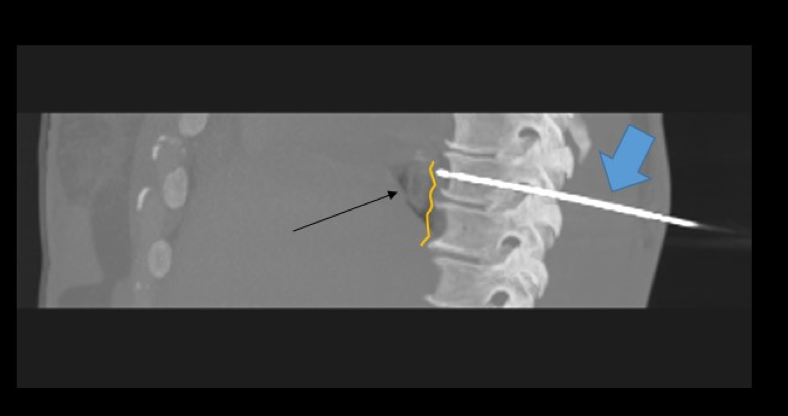

Figure. Reconstructed CT image from a cryovagotomy. The cryoablation probe (blue arrow) is placed through the skin under CT guidance to the posterior vagal trunk (yellow line), just posterior to the esophagus (black arrow).